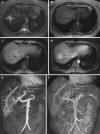

This pictorial review is based on our experience of the follow-up of 120 patients at our multidisciplinary center for hereditary hemorrhagic telangiectasia (HHT). Rendu-Osler-Weber disease or HHT is a multiorgan autosomal dominant disorder with high penetrance, characterized by epistaxis, mucocutaneous telangiectasis, and visceral arteriovenous malformations (AVMs). The research on gene mutations is fundamental and family screening by clinical examination, chest X-ray, research of pulmonary shunting, and abdominal color Doppler sonography is absolutely necessary. The angioarchitecture of pulmonary AVMs can be studied by unenhanced multidetector computed tomography; however, all other explorations of liver, digestive bowels, or brain require administration of contrast media. Magnetic resonance angiography is helpful for central nervous system screening, in particular for the spinal cord, but also for pulmonary, hepatic, and pelvic AVMs. Knowledge of the multiorgan involvement of HHT, mechanism of complications, and radiologic findings is fundamental for the correct management of these patients.